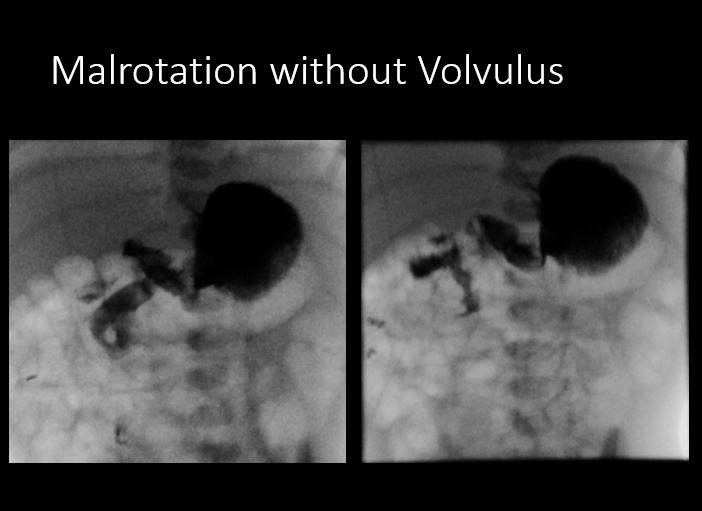

Info Images Findings Impression Reco/Acuity Case Images View Images / Launch Visage Case Notes History 2 week old male with bilious emesis. Exam FLUORO GI UPPER SERIES W/O KUB. Examination from the mouth/teeth to the ligament of Treitz and proximal jejunum. Prior Study None. Dicom View Reference Material

Section 1 Submit Findings CB1518 Findings Scout Image of the abdomen There is an NG/OG/FT tube which is malpositioned Yes No There is an unexpected radiopaque foreign body or incidental non-surgical foreign body in the abdomen or pelvis. Yes No There are additional lines, tubes, catheters or drains in place (examples include chest tubes, mediastinal drains, rectal temperature probe, etc.). Yes No There is dilatation with gas or fluid of multiple or diffuse loops of bowel. Yes No ​Both the small and large bowel are filled with air and/or fluid and may or may not be distended. Yes No There is a paucity of gas in the abdomen. Yes No There are centralized loops of small bowel with distention of the abdomen and pelvis. Yes No There is organomegaly. Yes No There are intra-abdominal calcifications. Yes No There is free air present. Yes No The visualized bones are abnormal. Yes No Fluoroscopic examination of the chest shows pneumonia, atelectasis, or cardiomegaly. Yes No The hemidiaphragmatic excursions are inequal and nonsynchronous. Yes No Procedural The patient was given thin barium/water soluble contrast to drink via bottle/syringe/sippy cup/straw/cup. A total of---mL of thin barium/water soluble was used for this examination. Yes No The exam is limited by patient motion or non-cooperativity. Yes No The exam is limited by small or inadequate boluses/contrast intake. Yes No The swallowing act is abnormal. Yes No There is tracheal aspiration. Yes No The course of the esophagus is abnormal. Yes No The caliber of the esophagus is abnormal. Yes No There is stenosis of the upper/mid/distal esophagus. Yes No There is dilatation of the upper/mid/distal esophagus. Yes No There is a tracheoesophageal fistula present. Yes No There is a filling defect. Yes No There is dysmotility of the esophagus. Yes No There is extrinsic mass effect. Yes No There is a vascular ring. Yes No The stomach does not fill readily. Yes No If the contrast is instilled via NG tube/gastrostomy tube/orogastric tube: There is abnormal contrast opacification of the stomach. Yes No The stomach empties abnormally. Yes No There is gastric outlet obstruction. Yes No The duodenal C-loop is abnormal in size. Yes No The location of the ligament of Treitz is abnormal. Yes No The proximal jejunum is dilated. Yes No There is gastroesophageal reflux observed to the upper/mid/distal esophagus. Yes No The reflux does not clear quickly. Yes No N/A